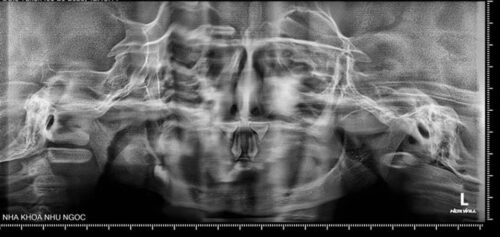

Hình 1: Ảnh chụp film – XQ

Tùy mức độ từ nhẹ đến nặng của bệnh mà có biểu hiện ở răng từ thiếu một vài răng đến thiếu nhiều răng đến không có răng.

Trường hợp thiếu răng: răng trong miệng thường bị dị dạng, có dạng hình nón hoặc hình chóp.

Do tình trạng giảm tiết nước bọt trong miệng nên các trường hợp khiếm khuyết men răng và sâu răng xảy ra thường xuyên.